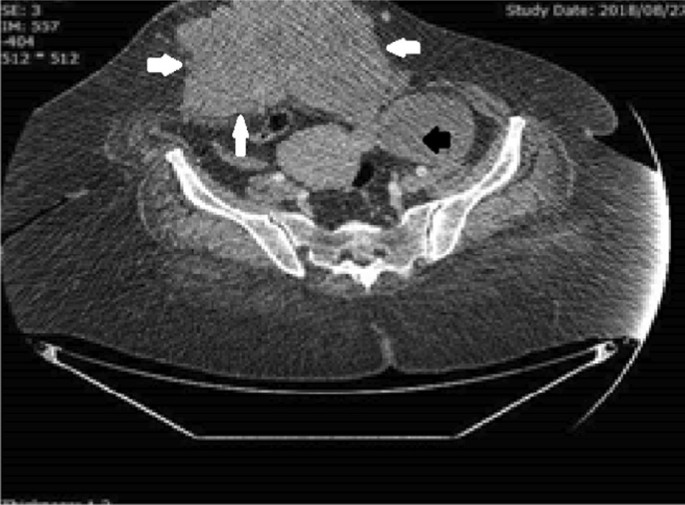

A 58-year-old Iranian postmenopausal woman referred to the hospital because of a abdominal wall mass and hernia. She had a history of three cesarean sections with a midline abdominal incision. Her last cesarean section was performed 20 years earlier. Physical examination demonstrated a partially mobile and large mass in the anterior abdominal wall in the midline cesarean scar, extending bilaterally to the midclavicular line. The upper margin of the mass was adjacent to her umbilicus, where there was a large umbilical hernia above the mass (Fig. 5). Pelvic ultrasound showed an irregular 12 × 8 × 8 cm mass in the abdominal wall anterior to the rectus muscle involving subcutaneous tissue, a large umbilical hernia containing omentum, and a well-defined left solid adnexal mass (4.1 × 3.7 × 5.1 cm in diameter). An abdominopelvic CT scan confirmed the ultrasound findings (Fig. 6). The peritoneal surface of the anterior abdominal wall was intact, and other abdominal and pelvic organs were normal. The chest X-ray was normal.